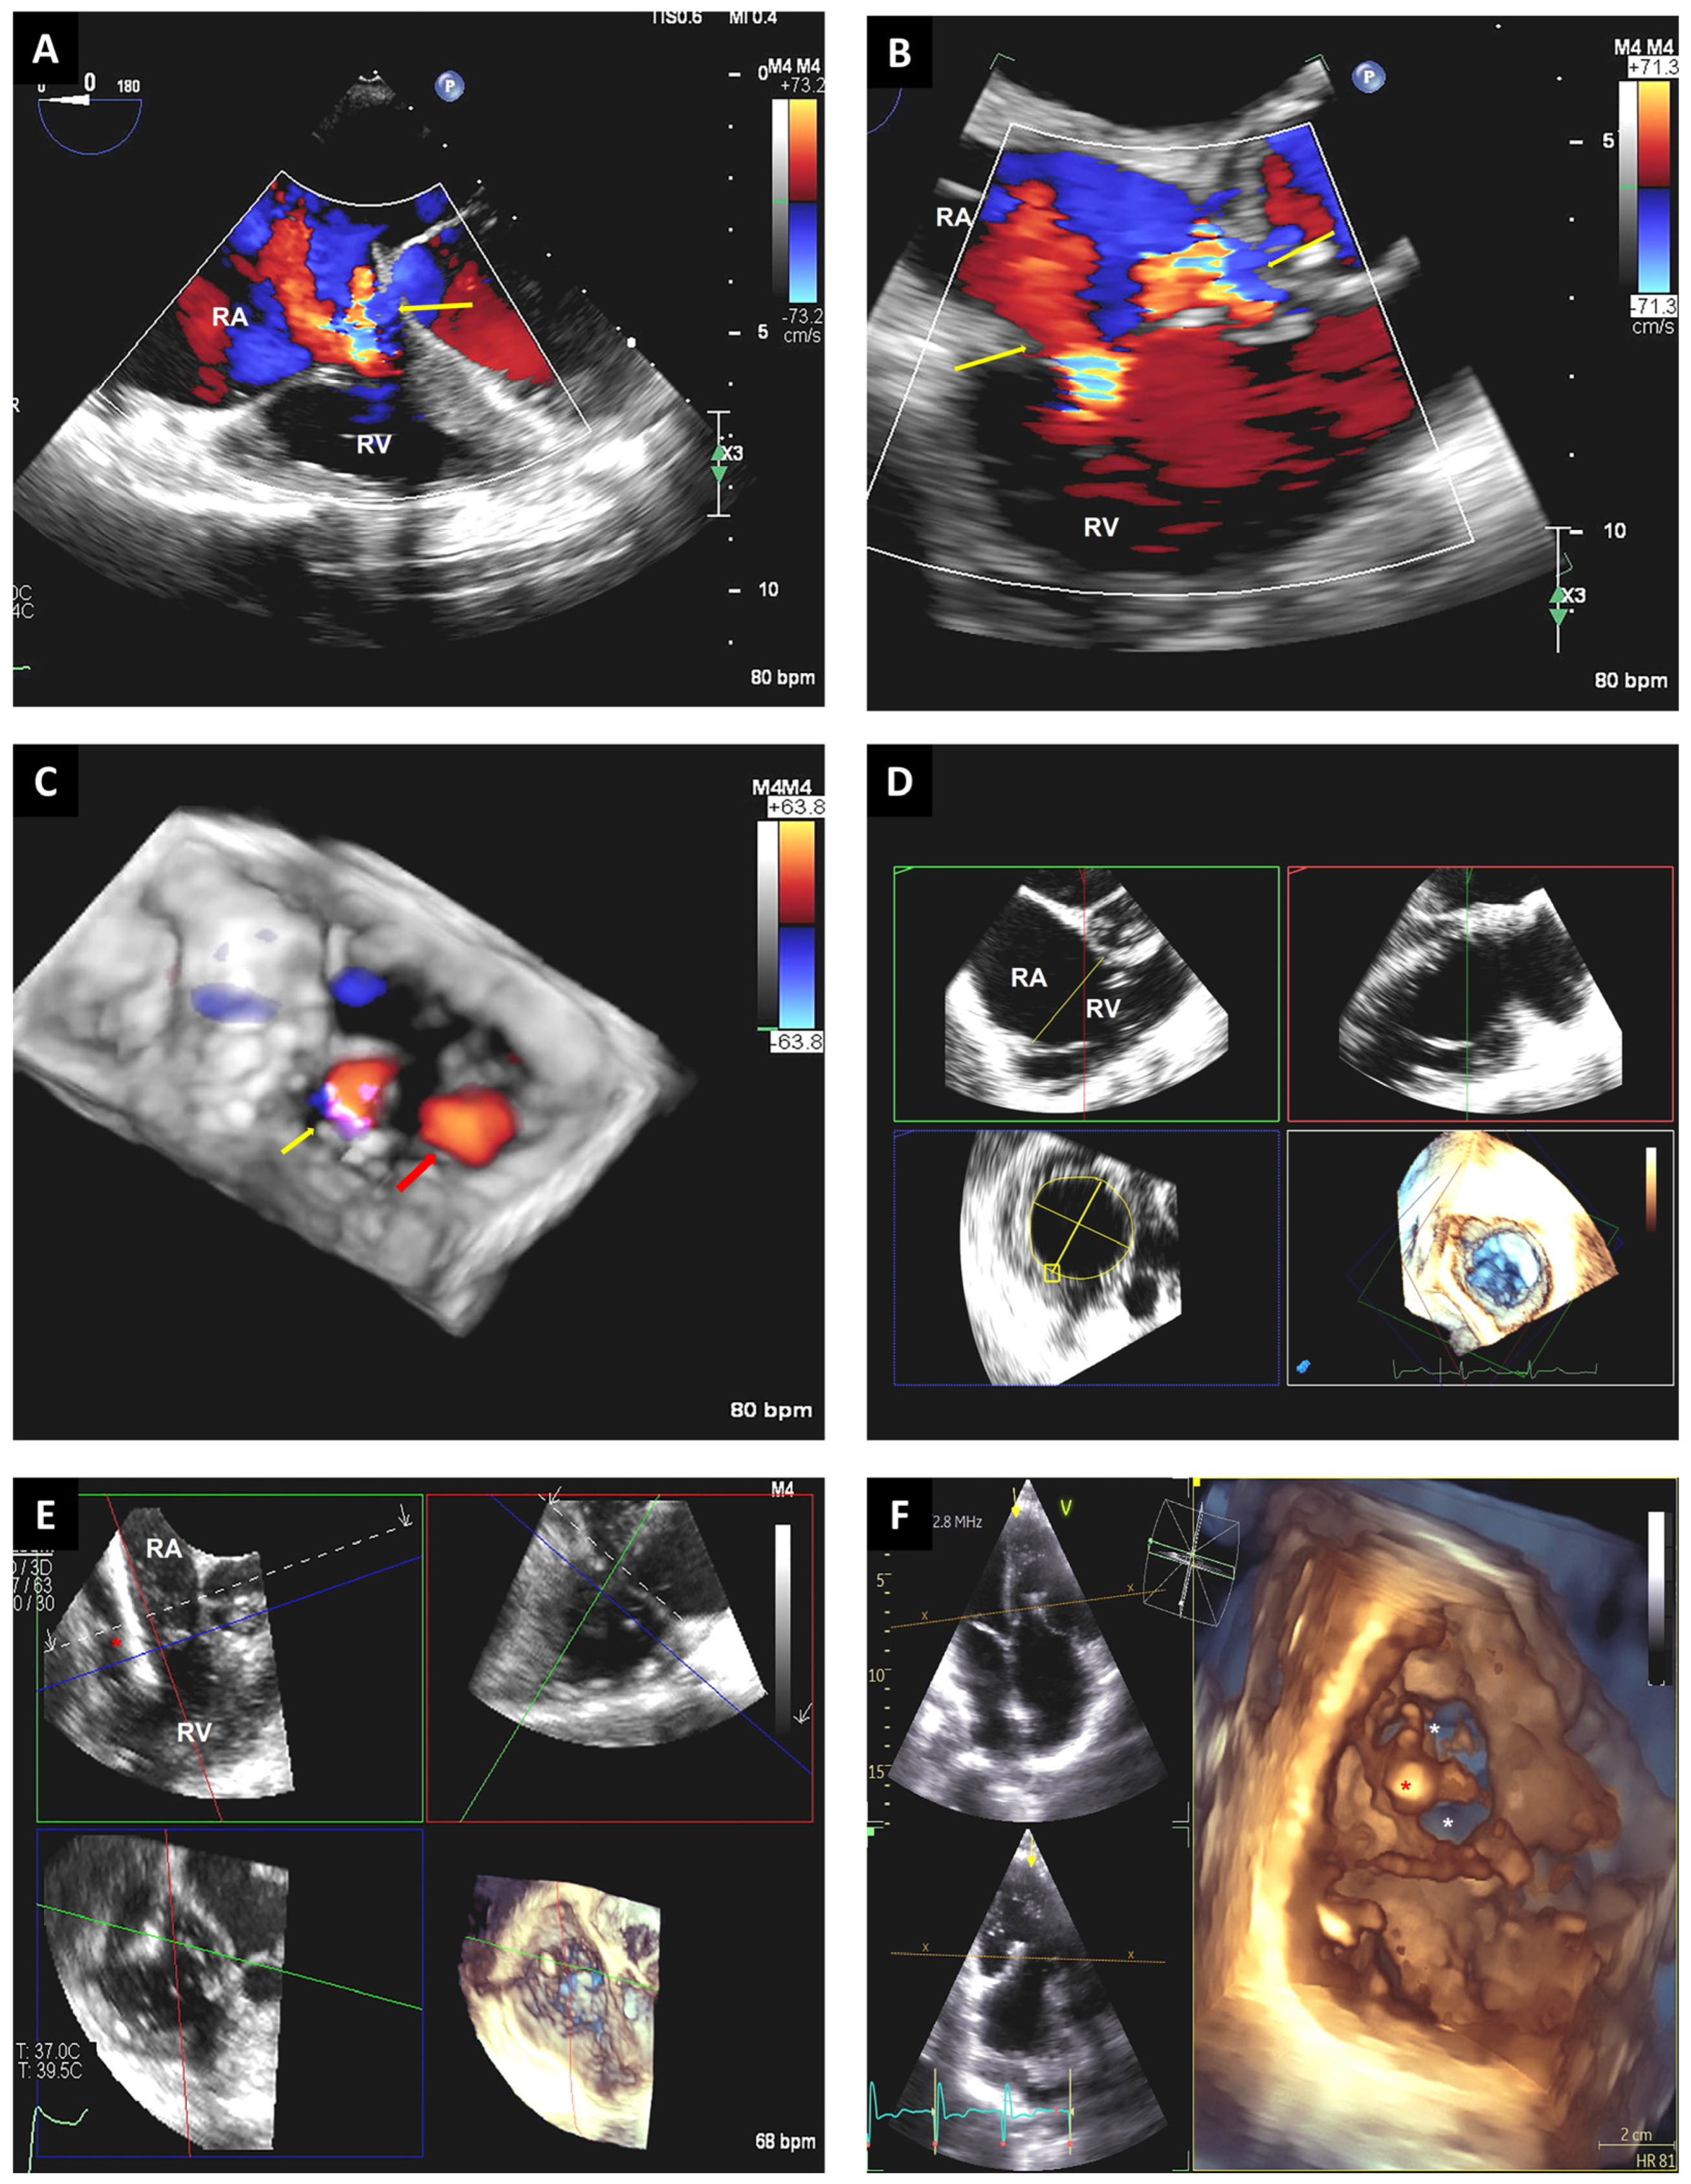

3.4. Tricuspid Valve Interventions